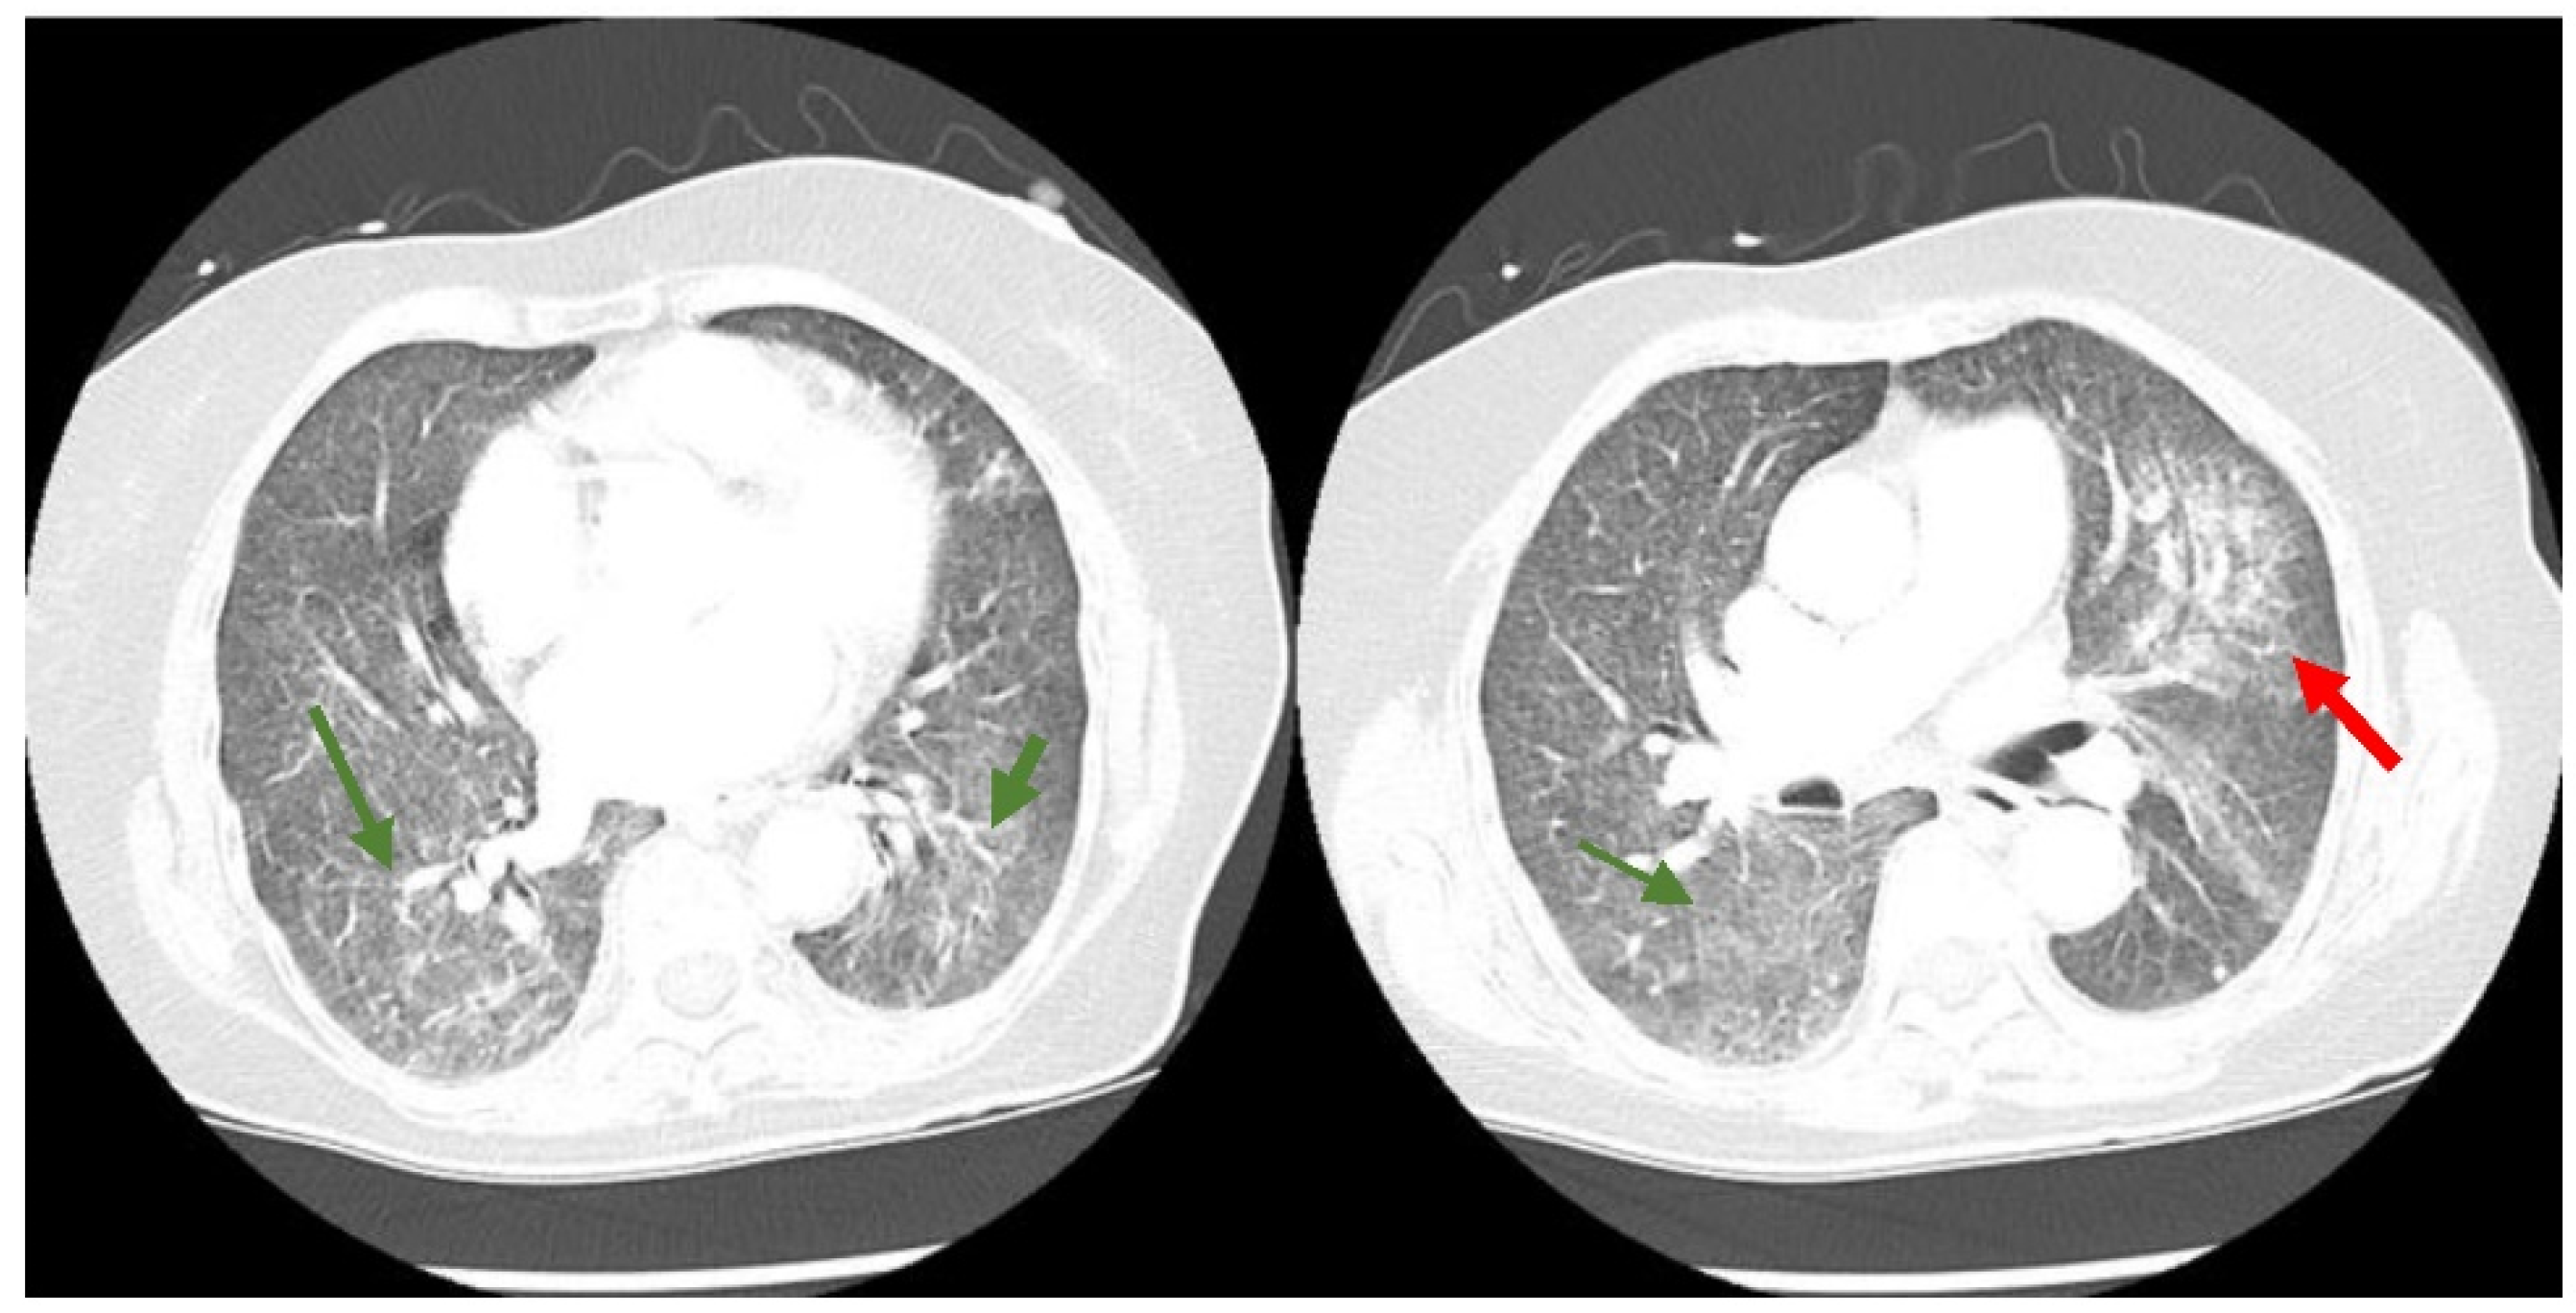

A 74-year-old Filipino female with a medical history significant for hypertension, hyperlipidemia, and non-insulin-dependent type II diabetes presented to the emergency department (ED) of a South Florida hospital with a one-week history of increased generalized weakness and worsening shortness of breath. Three months prior, the patient was treated in the hospital for COVID-19 with intravenous dexamethasone and remdesivir, and was discharged home with oxygen. She fully recovered to her baseline and no longer required supplemental oxygen two months before the above onset of symptoms. On arrival to the ED, she was lethargic, but not in severe distress. She had an oral temperature of 37.5 °C, a heart rate of 97 beats/min, blood pressure of 133/78 mmHg, a respiratory rate of 20 breaths/min, and oxygen saturation of 91% on 3 L nasal cannula supplemental oxygen. She had decreased breath sounds bilaterally and rales at the bases. Her heart sounds were distant without any murmurs and she had no peripheral edema. The initial laboratory results are available in Table 1. Her chest X-ray showed a left mid-lung infiltrate that was new compared with the X-ray three months prior (Figure 1). The computed tomography (CT) chest scan with IV contrast showed no evidence of a pulmonary embolism. However, it revealed significant bilateral infiltrates (Figure 2) that had progressed from her previous CT chest scan three months prior (Figure 3). Her echocardiogram revealed an ejection fraction of 39% and no other structural abnormalities.

Figure 2. CT chest scan with diffuse ground glass opacities throughout both lungs more extensive than present on prior imaging (green arrows) with a superimposed patchy airspace consolidation in the perihilar region of the left upper lung lobe (red arrow).